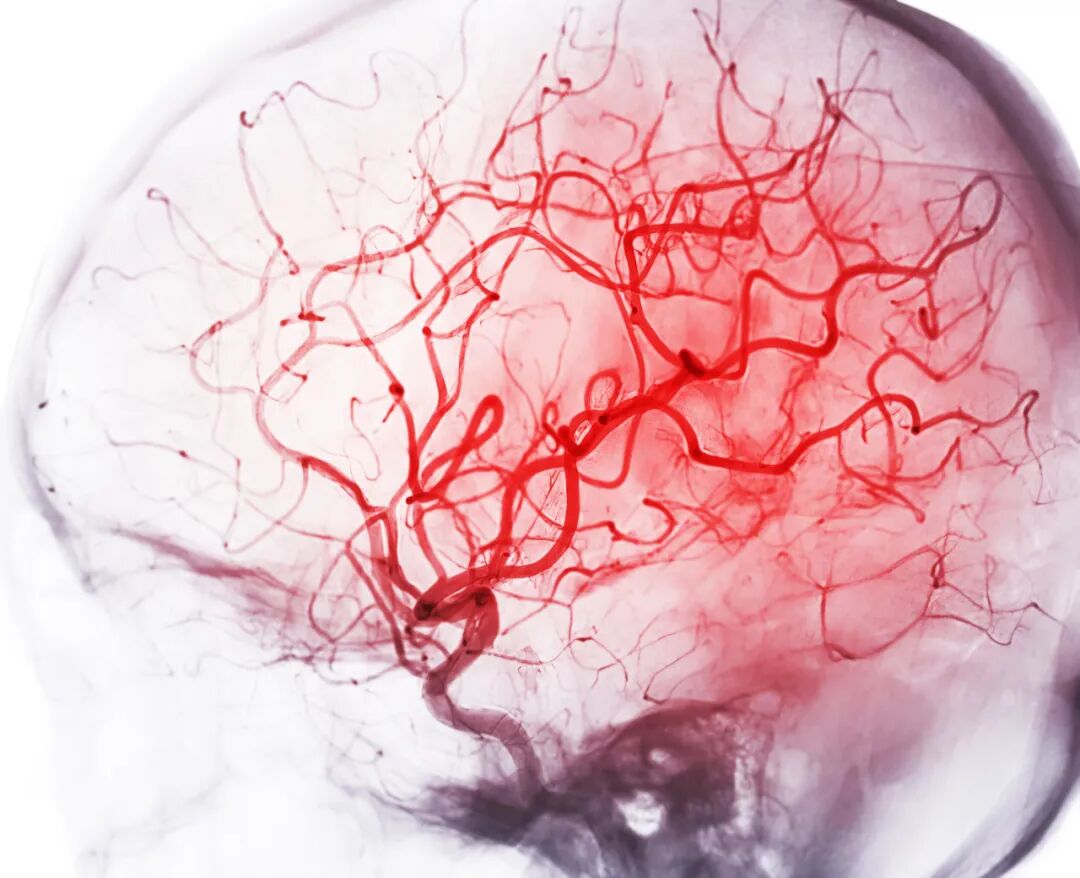

近日,我院呼吸治疗科在正式成立之初,便完成一次高效协作的实战检验——成功为一名脑干出血、经口气管插管行机械通气的患者,实施了床旁精准、微创、全程可视化纤支镜引导下经皮旋转气管切开术。

患者因脑干出血入院,已行经口气管插管机械通气。

脑干是控制呼吸、心跳的“生命中枢”,此处出血病情极其危重、变化迅速。长期经口插管不仅增加痛苦,也易引发感染、损伤声门,且不利于气道管理和康复过渡。